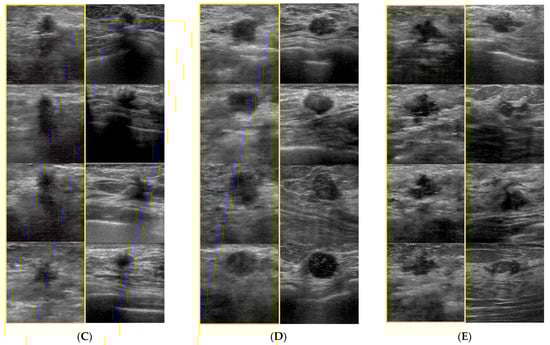

- Fujioka, T.; Mori, M.; Kubota, K.; Kikuchi, Y.; Katsuta, L.; Adachi, M.; Oda, G.; Nakagawa, T.; Kitazume, Y.; Tateishi, U. Breast ultrasound image synthesis using deep convolutional generative adversarial networks. Diagnostics 2019, 9, 176. [Google Scholar] [CrossRef] [PubMed]

- Fujioka, T.; Kubota, K.; Mori, M.; Katsuta, L.; Kikuchi, Y.; Kimura, K.; Kimura, M.; Adachi, M.; Oda, G.; Nakagawa, T.; et al. Virtual interpolation images of tumor development and growth on breast ultrasound image synthesis with deep convolutional generative adversarial networks. J. Ultrasound Med. 2021, 40, 61–69. [Google Scholar] [CrossRef] [PubMed]